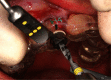

Anterior aesthetic zone implant placement and tooth restoration can be a quite challenging procedure. Modern technology offers new tools that can help maximize results in both aesthetic and functional ways. The socket-shield technique, as described by Hürzeler et al., boosted with the 3D diagnostics, digital planning, and 3D printing, could provide a valuable alternative to traditional approaches. This case report describes a clinical workflow for an efficient anterior implant-prosthetic restoration.